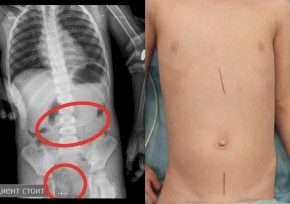

Бүлдіршіннің анасы ұлының ине жұтып қойғанын айтып, балалар ауруханасының қабылдау бөліміне келген. Кейін дәрігерлер іш қуысын шолу рентгенограммасы арқылы тексеріс жүргізген. Онда асқазанның проекциясынан болжаммен жүгірткі мен екі тігін инесі табылған.

"Кейінірек құрсақ қуысының бақылау R-граммасында құрсақ қуысының жоғарғы сатысынан тағы екі ине және жамбас проекциясынан бір ине табылды. Қайта ЭФГДС жасалып, ине асқазаннан алынды. Кейін колоноскопия арқылы сигма тәрізді ішекке бекітілген тағы бір ине алынды", – дейді жоғары санатты хирург Сейдахмет Чинибеков.

Алайда бұдан кейін баланы бақылау кезінде құрсақ қуысының R-граммасында жамбас проекциясынан төртінші ине де табылған. Кері колоноскопия жасалып, соңғы ине сигма тәрізді ішектен ішектің шырышты қабығы тұсынан алынды. Қазіргі уақытта бала қанағаттанарлық жағдайда үйге шығарылған.